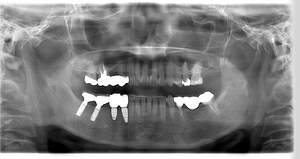

インプラント治療の症例4

レントゲン写真

- Befor

- After

| 年齢 | 50代・男性 |

|---|---|

| 主訴 | 部位:左下6番7番 主訴:左下奥歯腫れて痛い。 |

| 治療内容 | 左下6番抜歯、左下6番7番骨造成、インプラント埋入 |

| 治療費 | 合計:1,232,000円 ・内訳 診断料:55,000円 サージカルガイド2本:66,000円 GBR:110,000円×2本 埋入料:165,000円×2本 静脈内鎮静麻酔:77,000円 2次OPE:22,000円×2本 仮歯:55,000円×2本 上部構造(フルジルコニア):165,000円×2本 (2023年1月現在) |

| 治療期間 | 約8ヶ月 |

| 治療方針 | 元々支台歯に負荷がかかりやすいとされている延長ブリッジを抜歯し、1本単体でしっかりかめるようにインプラントを2本埋入した。骨吸収も進んでいたため、※GBR法で骨造成を同時に行った。 治療と並行して、全顎的な歯周病治療も行い、今後は歯周病が進行しないよう、こまめにメンテナンスに通っていただく。 |

| 特記事項 | ※1 GBR・・・骨再生誘導法。骨の高さや厚みを人工骨や人工膜などを使用し再生する方法 |

| 担当者所見 | 6番は歯根分割された被せ物が7番の欠損部との延長ブリッジとされており、強い咬合と歯周病も相まって負荷がかかり動揺し、歯として機能しなくなったため、抜歯となった。 |